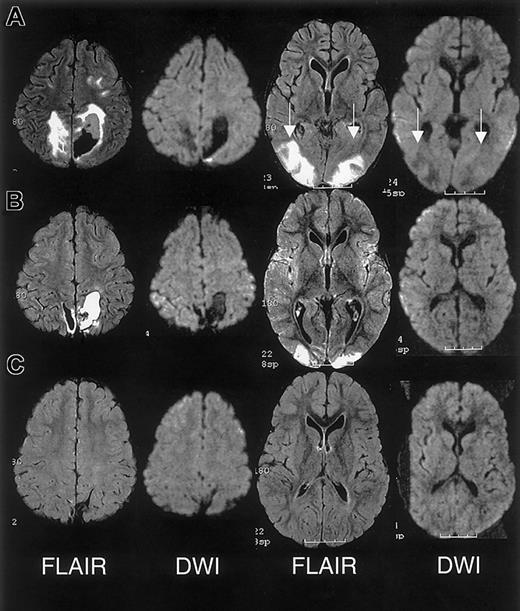

The initial clinical reading of the MRI, 1 day following endotracheal extubation, was bilateral ischemic infarcts and biparietal hemorrhages. The subsequent research reading of the initial MRI and follow-up MRI at 1 month and 15 months following discharge revealed findings consistent with RPLS complicated by hemorrhage; there was no evidence of infarction (Figure 3).

MRI findings for case 3.

(A) Extensive areas of FLAIR T2-weighted signal hyperintensity in the subcortical white matter and overlying gray matter of the posterior, frontal, and occipital lobes. Parenchymal hemorrhage was seen in the high parietal region predominantly on the patients's left. (B-C) Follow-up MRI scan 1 month and 15 months following discharge showed progressive evolution and resolution of the T2 signal hyperintensities with residual encephalomalacia in the left parietal region. These findings were consistent with reversible posterior leukoencephalopathy complicated by hemorrhage; there was no evidence of infarction.

RPLS is difficult to distinguish from acute cerebral infarcts clinically and radiographically. The distinction is important because cerebral infarction implies irreversible damage and warrants blood transfusion therapy for an indefinite period. Conversely, RPLS is potentially reversible but may require judicious hypertensive management. In this case series, 2 patients were originally diagnosed as having cerebral infarcts according to the clinical reading of the MRI, one of whom was subsequently determined to have RPLS and the other with cerebral hemorrhage. Appropriate MRI techniques and interpretation play a key role in differentiating RPLS from cerebral infarct (Figure 4). Both RPLS and cerebral infarct present with T2-weighted hyperintensities. DWIs typically show hyperintense signal in cerebral infarcts, whereas DWIs in RPLS are ambiguous because of T2 shine-through effects.8 14 Producing images of the diffusion coefficient eliminates this ambiguity.

Characterization of T2-weighted hyperintensities on MRI of the brain distinguishing cerebral infarct from reversible posterior leukoencephalopathy syndrome (RPLS).

DWI indicates diffusion weighted image; DC, diffusion coefficient.